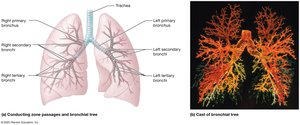

Bronchial Tree

Primary bronchi branch into secondary (lobar) and tertiary (segmental) bronchi

Bronchioles: Smallest airways, lack cartilage, lined by simple cuboidal epithelium

Terminal bronchioles: Final part of conducting airways

Lung Structure

Lungs are divided into lobes and further into pulmonary lobules by connective tissue partitions (trabeculae and interlobular septa)

Each terminal bronchiole supplies a pulmonary lobule

Respiratory bronchioles connect to alveoli via alveolar ducts and sacs